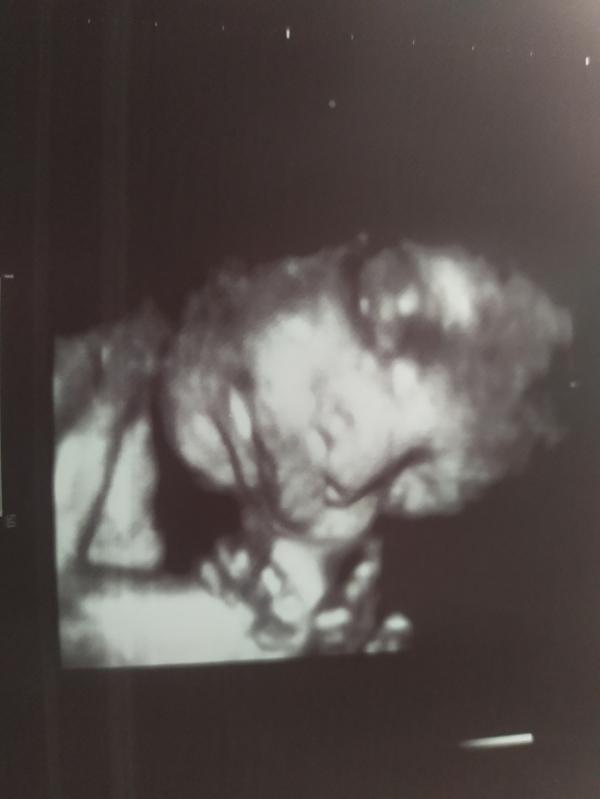

post image

32 недельки ждём сыночка